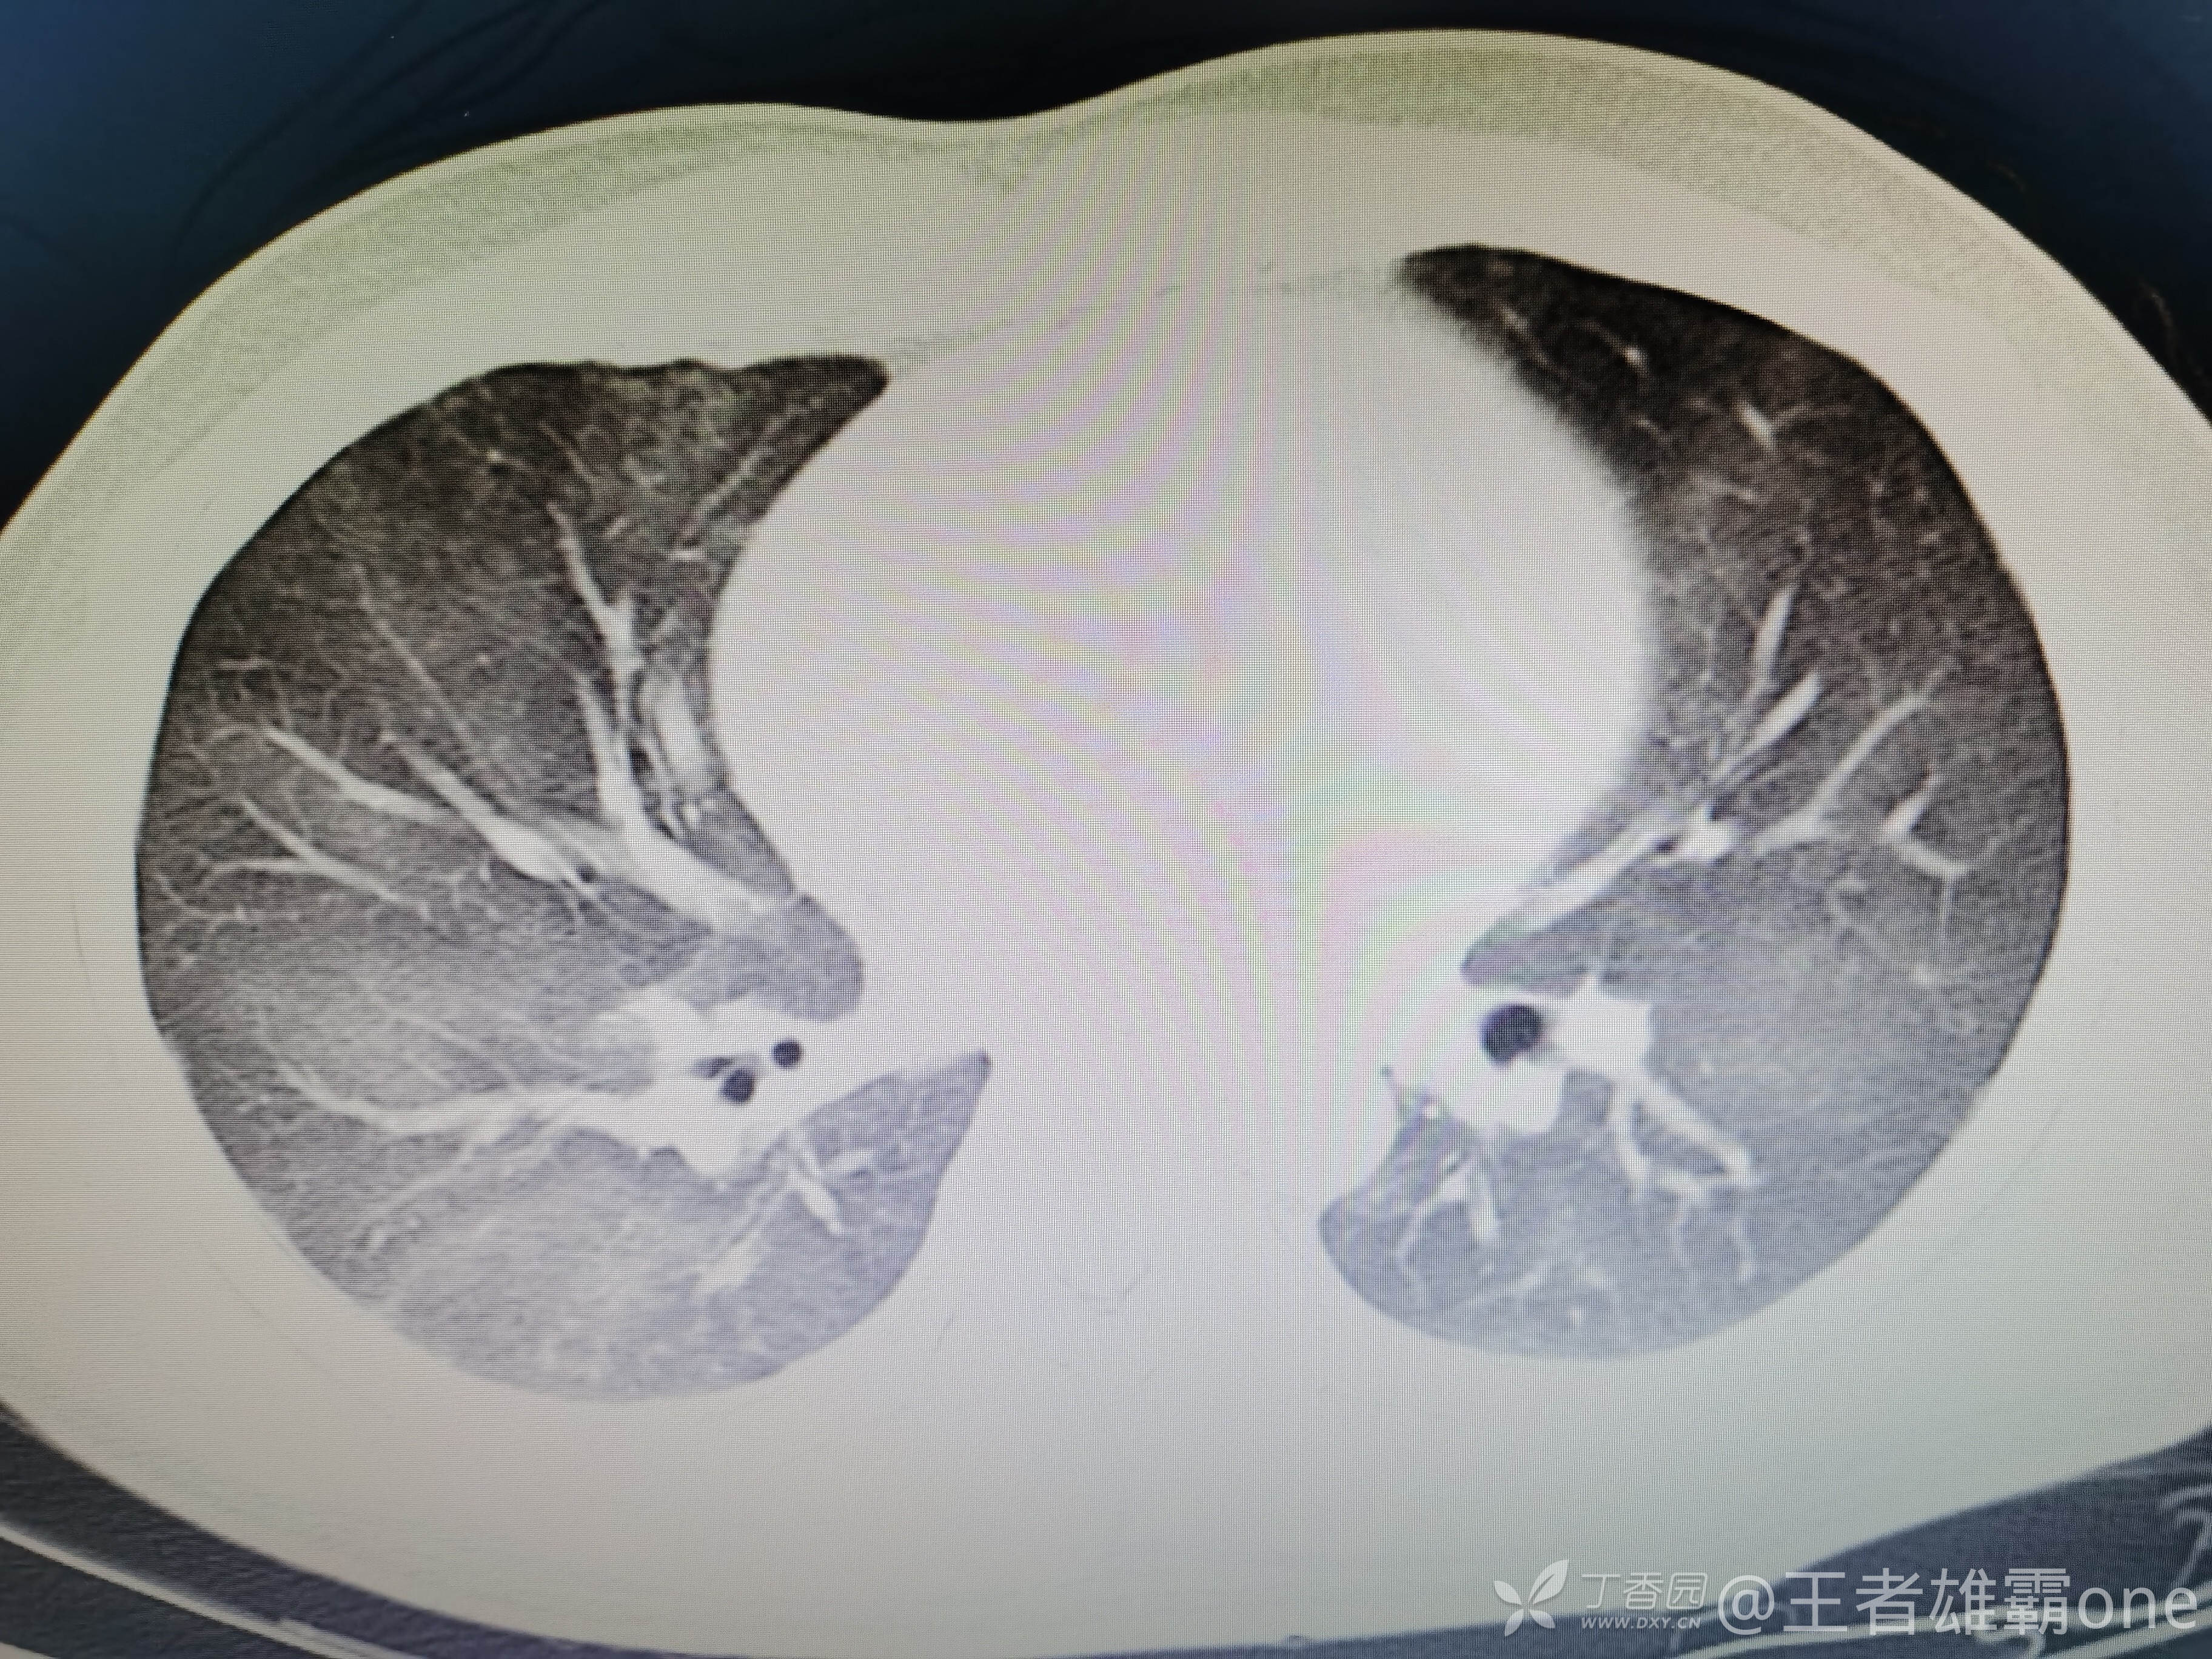

西门开心 推荐男,33岁,否认既往有心脏基础疾病,6-1受伤后急诊行右胫腓骨骨折固定术(术前胸部CT无明显异常,见后面视频前半部分),术后逐渐出现刺激性咳嗽、胸闷,无精神症状,无皮疹,无胸痛,无咯血等。6-6完善胸部CT、脑钠肽前体、心超等辅查,其中脑钠肽前体、心超无明显异常。复查的胸部CT见视频后半部分:

附几张CT图片: